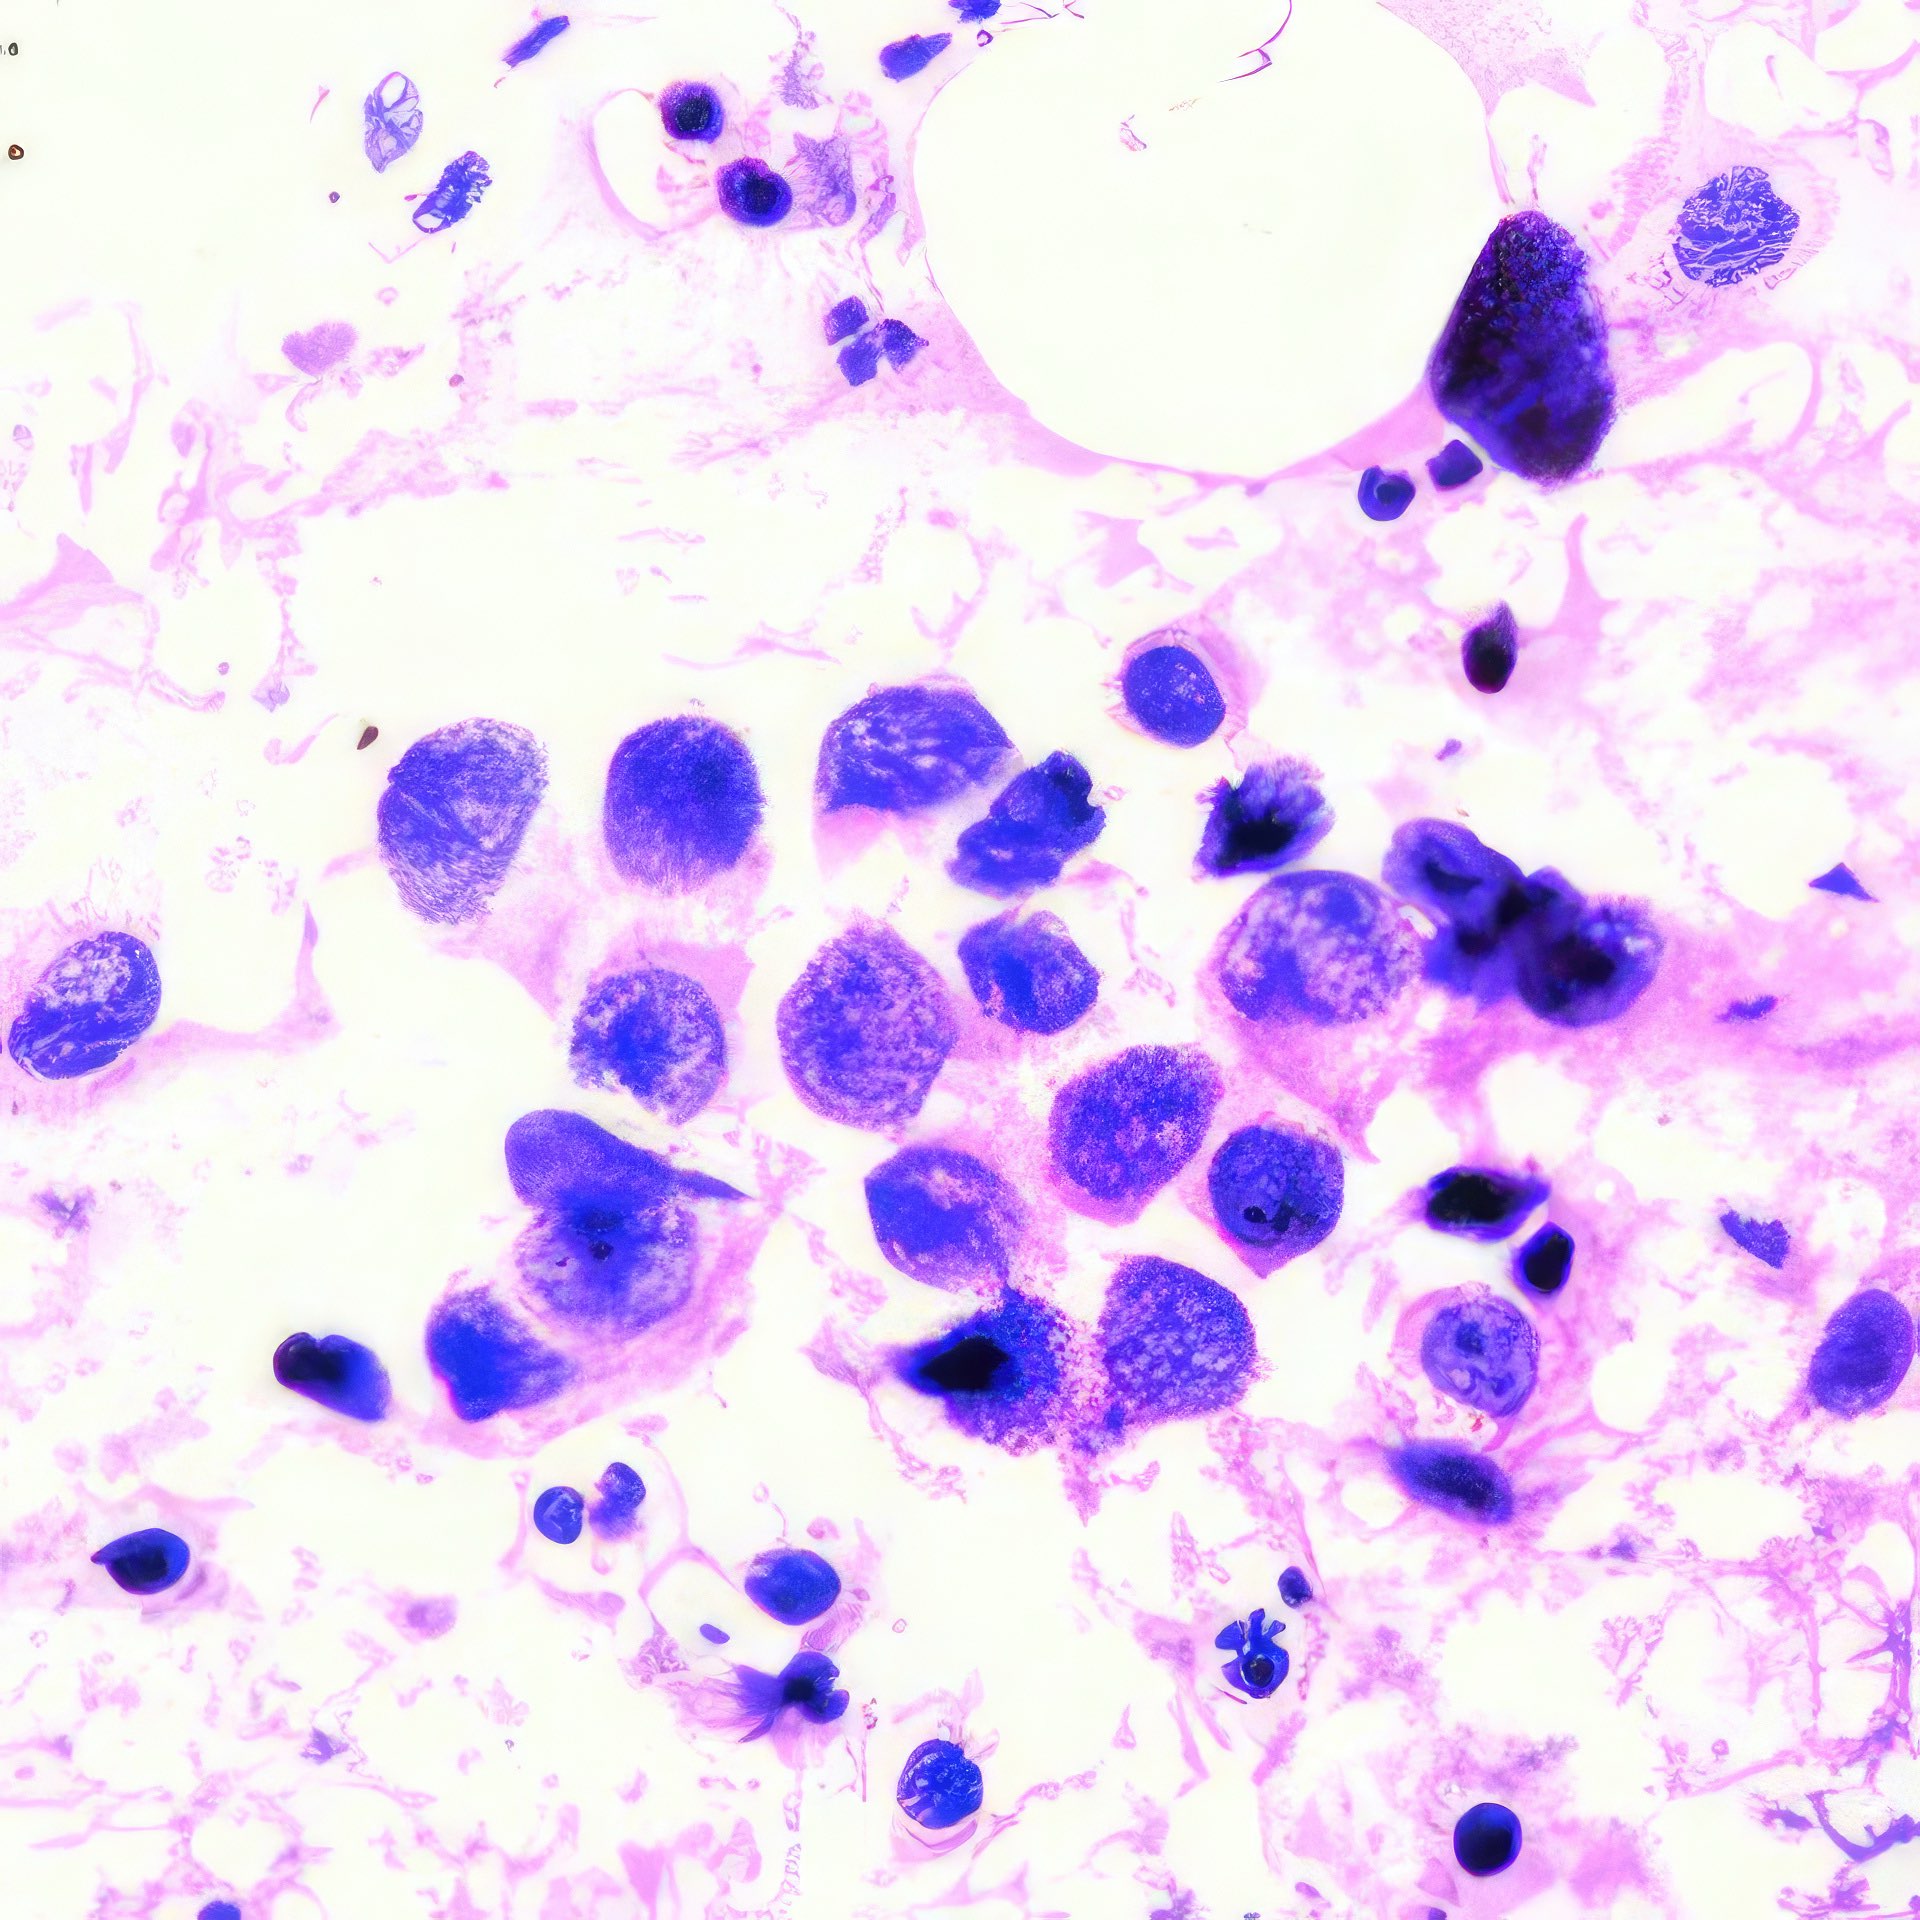

Frau, 60 Jahre

Linkes Brustödem mit Veränderung der areolären Haut seit 3 Jahren,

axilläre Lymphadenopathie und linkes Handödem seit 2 Monaten.

(Abbildungen 3 - 6: Pap, Vergrößerung 1000x)

Makroskopisch zeigt die areoläre Haut (Brustwarzenhof) eine feine ekzemartige nässende granuläre Struktur; die Brustwarze ist nicht eingezogen (Abb. 1 und 2). Die extrem atypischen Zellen liegen verstreut (Abb. 3), oder bilden lose zusammenhängende Gruppen (Abb. 4, 6). Einige sind doppelkernig. Im Vergleich zum gewöhnlichen Mammakarzinom sind sie extrem pleomorph und ihre Kerne sind stärker hyperchromatisch, sehr grob strukturiert, und zeigen manchmal prominente Chromozentren. Das Zytoplasma ist unterschiedlich breit und erscheint manchmal als vakuolär.

Histologie

Das durch Stanzbiopsie gewonnene histologische Präparat zeigt viele große, scheinbar vakuolisierte Zellen innerhalb des Plattenepithels. Eine PAS-Färbung war nicht möglich.

Die zytologischen und histologischen Befunde sind charakteristisch für das Paget-Syndrom. Histologisch würden die Zellen PAS-positiv sein. Das Brustödem, die nicht eingezogene Brustwarze und die axilläre Schwellung weisen auf ein tiefsitzendes Karzinom hin, das bereits in die axillären Lymphknoten metastasiert hat. Die Kombination von Karzinom und Morbus Paget ist nicht ungewöhnlich 1. - Die extrem atypischen Zellen können zu einer Verwechslung mit einem Plattenepithelkarzinom führen 2. Andererseits unterscheidet dies die Zellen des Morbus Paget von denen des Adenoms, das ebenfalls in der areolären Region auftritt 3, 4. Schließlich können die makroskopisch erscheinenden vesikulären Strukturen einen Pemphigus vulgaris, eine Autoimmunerkrankung der Haut, simulieren 5.